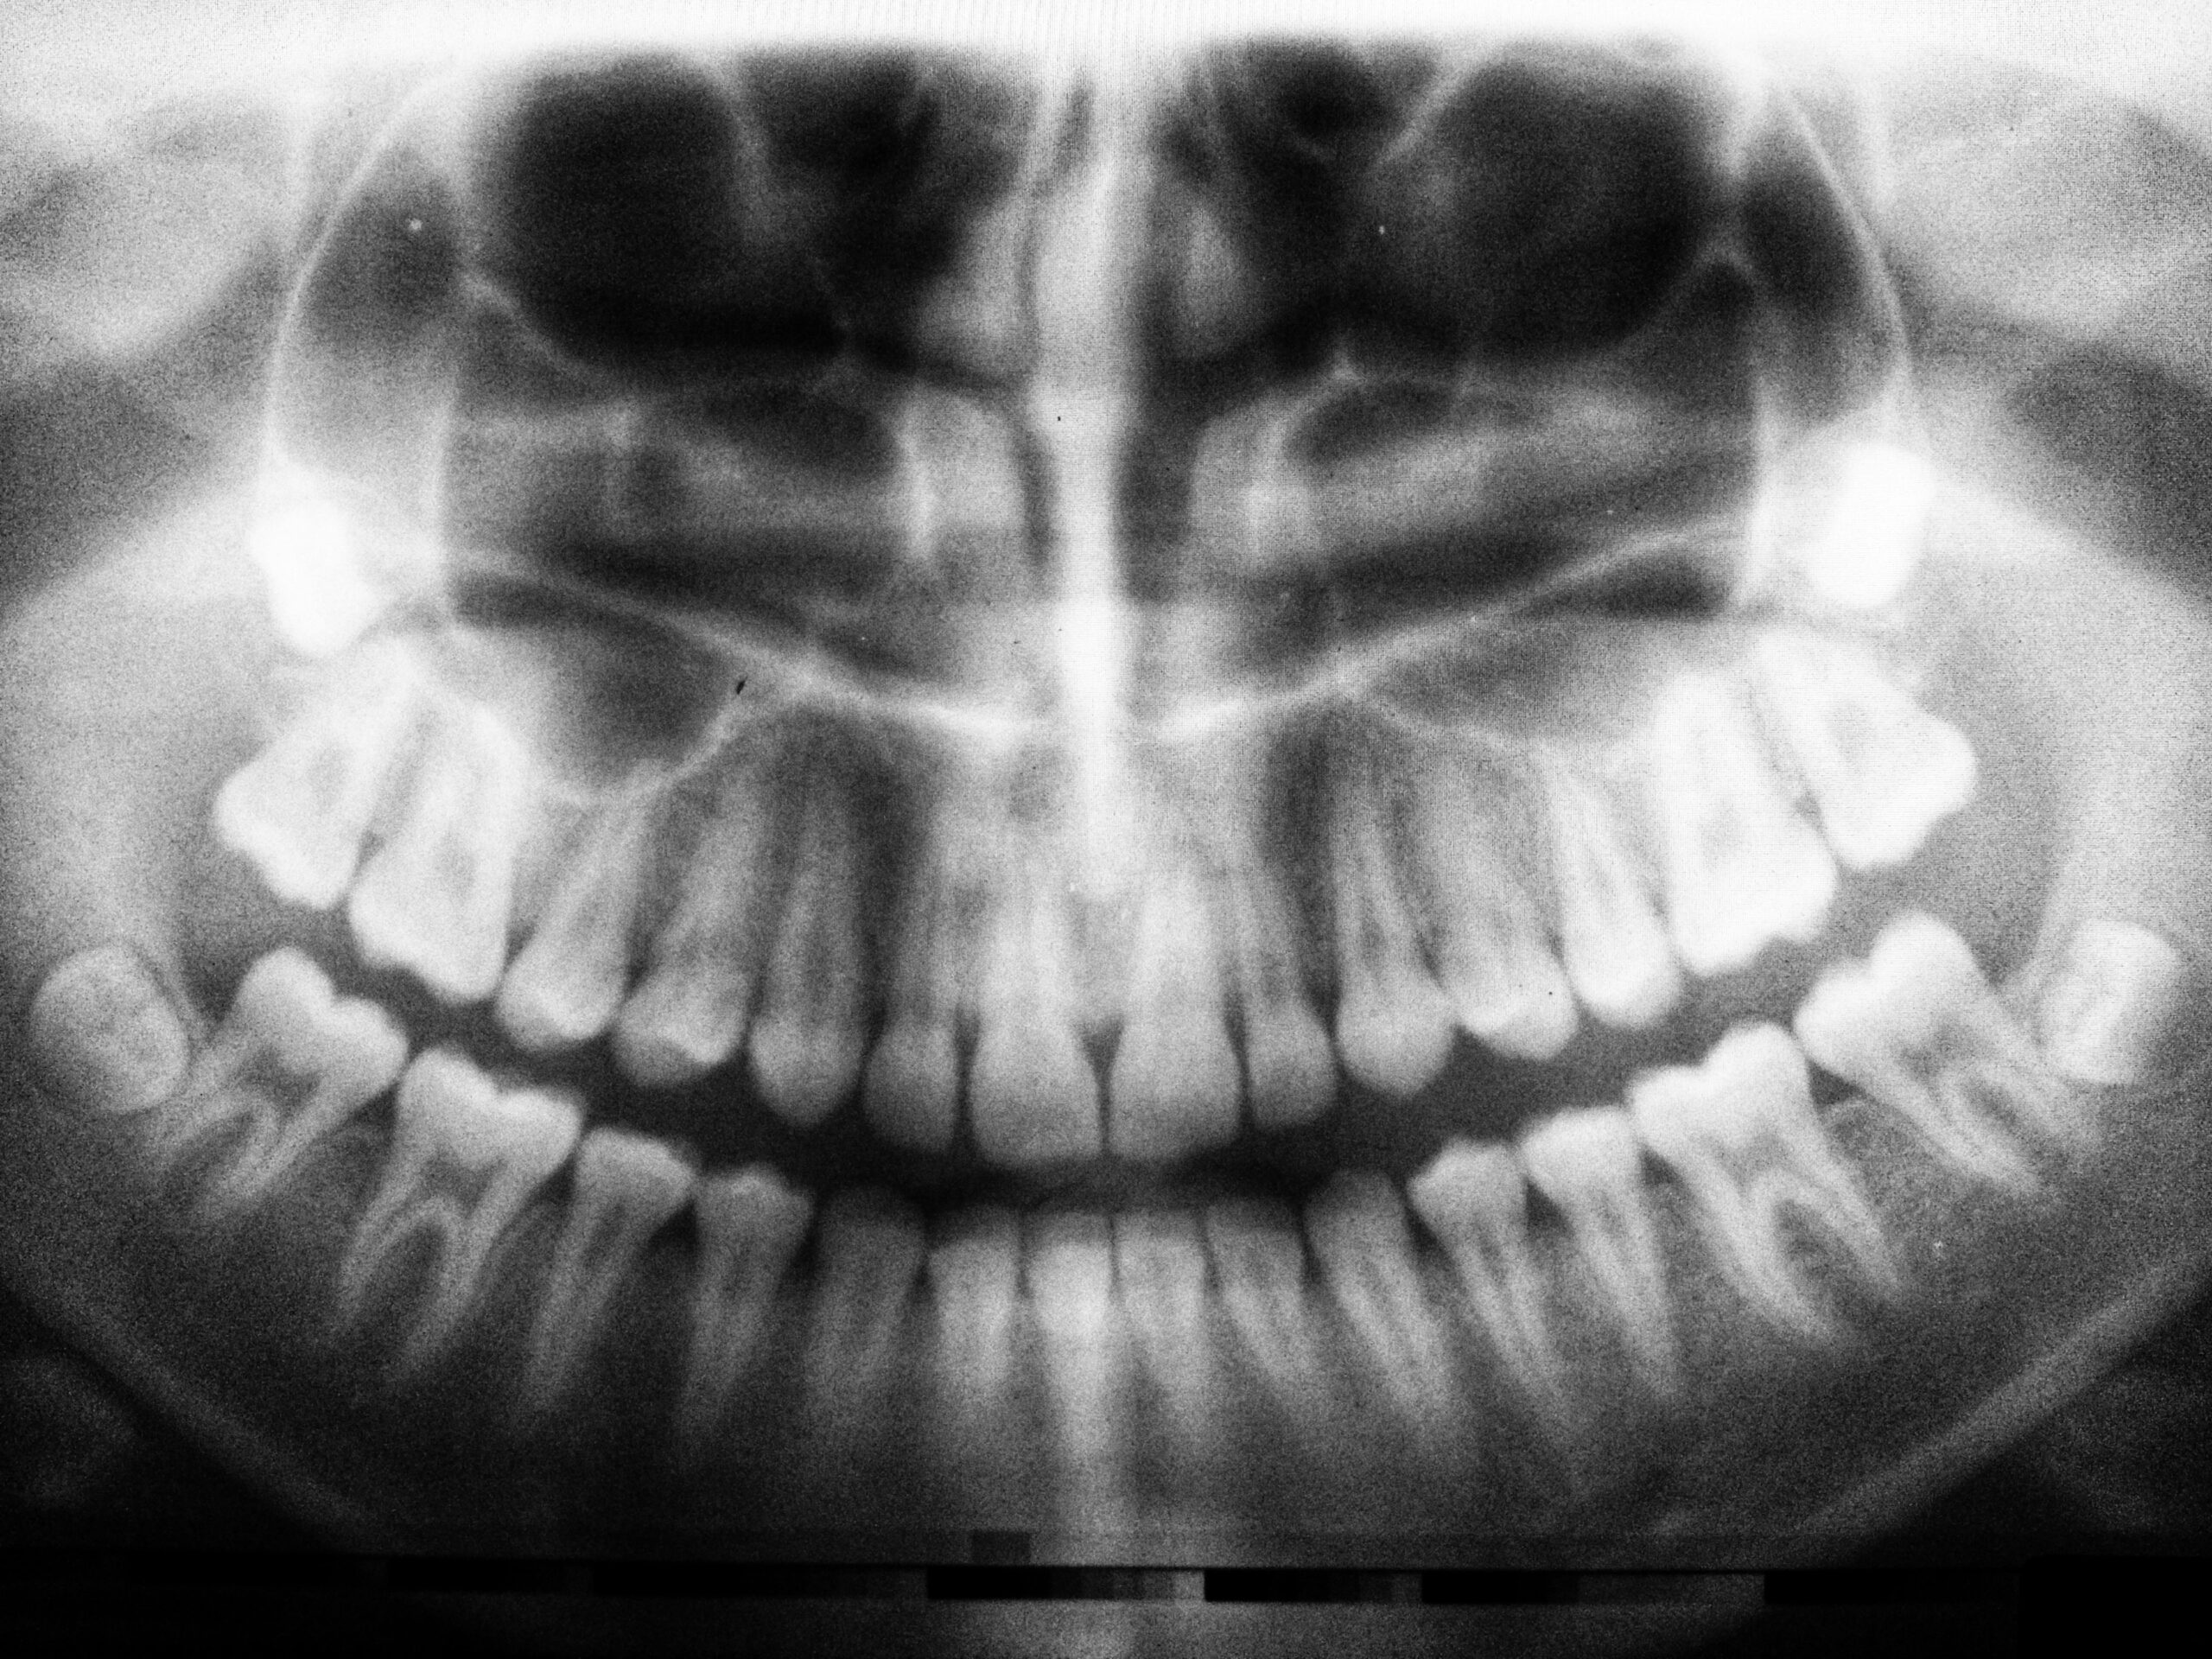

• Pantomogram: Pantomogram to kompleksowe zdjęcie rentgenowskie całej jamy ustnej, umożliwiające identyfikację zmian patologicznych oraz planowanie leczenia.